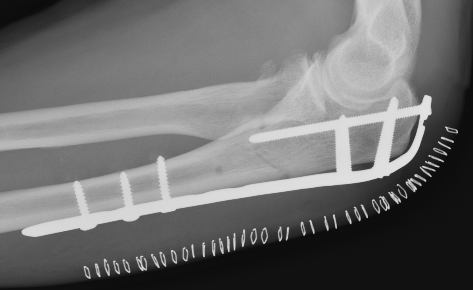

ORIF with olecranon plate

Indication

Fracture distal to center of rotation of elbow / trochlea

Technique

Lateral decubitus with tourniquet

- curvilinear incision to avoid prominence of olecranon

- identify and protect ulna nerve

- reduce fracture with arm in extension

- ensure articular congruity

- use anatomical precontoured plate

- may want to split distal triceps to reduce proximal plate prominence